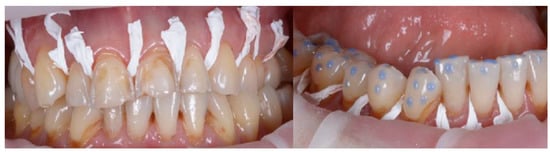

2.2. Clinical Example

2.3. Outcome Achieved